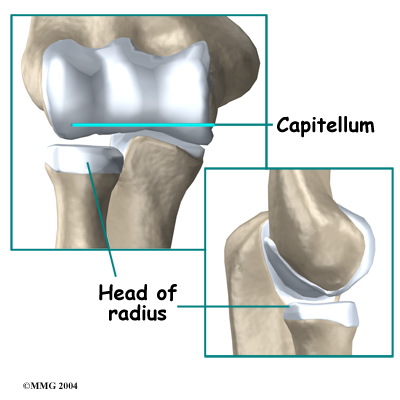

The joint where the humerus meets the radius is called the humeroradial joint. This joint comprises a bony knob and a shallow cup. The knob on the end of the humerus is called the capitellum. The capitellum fits into the cup-shaped end of the radius. This cup is called the head of the radius.

When the head of the radius spins on the capitellum, the forearm rotates to turn the palm up toward the ceiling (supination) or down toward the floor (pronation). The joint also hinges as the elbow bends and straightens.

In the elbow joint, the ends of the bones are covered by articular cartilage — a slick, smooth, fibrous material. Articular cartilage protects the bone ends from creating friction when they rub together as the elbow moves. The cartilage is also soft enough to act as a shock absorber. If articular cartilage is protected from injury, it is robust enough to last a lifetime.

Elbow OCD affects the articular cartilage in the capitellum. It also impacts the layer of bone just below the cartilage, which is called the subchondral bone. In advanced stages of OCD, the upper end of the radius, particularly the head of the radius, is also affected.